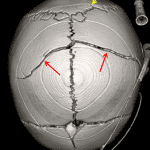

- Bilateral nondepressed parietal bone fractures extending to the sagittal suture bilaterally and to the squamosal suture on the left. Additional small nondepressed occipital fracture just caudal to the lambda, which extends to the left lambdoid suture

Bilateral nondepressed parietal bone fractures extending to the sagittal suture bilaterally and to the squamosal suture on the left. Additional small nondepressed occipital fracture just caudal to the lambda, which extends to the left lambdoid suture. No sutural diastasis.